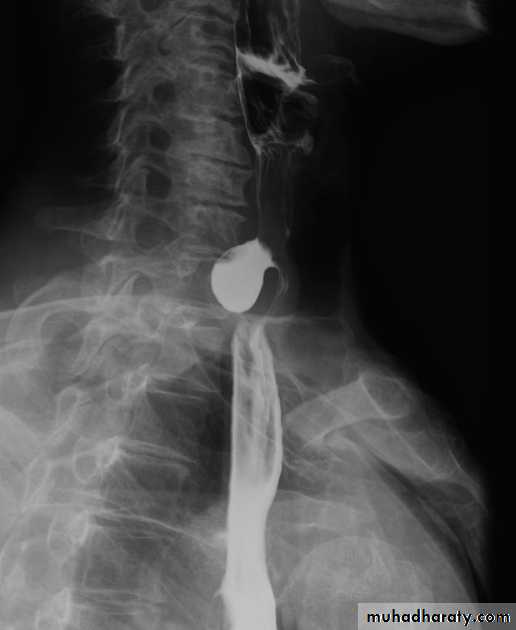

Webs

Majority protrude from anterior esophageal wall

short, thin web (arrows) with minimal intraluminal extension.